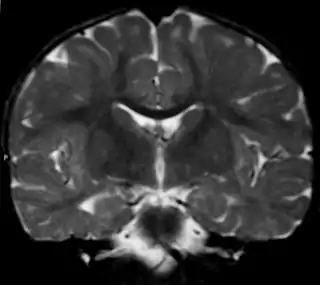

![]() Imagen de una leucodistrofia en una niña de 18 meses. Posible Enfermedad de Alexander | ||

El diagnóstico había sido durante mucho tiempo difícil, debido a que la mayoría de los signos podían darse también en otras leucodistrofias, de modo que la prueba diagnóstica de confirmación consistía en una biopsia cerebral que revelara las fibras de Rosenthal. En ocasiones esto se efectuaba post mórtem en la necropsia. Sin embargo, esta prueba resulta bastante invasiva y se vio la necesidad de buscar otras posibilidades aprovechando las nuevas técnicas de imagen por MRI. En marzo de 2001 la eminente neuróloga Marjo van der Knaap y su equipo pudieron establecer una serie de criterios que probaban en un 90% de los casos la existencia de la enfermedad.[11] Se considera que la presencia de al menos 4 de los siguientes criterios dan un resultado diagnóstico positivo:

- Presencia de anormalidades extensas en la materia blanca con una preponderancia frontal o bien en cuanto a la extensión de estas anormalidades, en el grado de abultamiento, en el grado de cambio de señal o en el de pérdida de tejido (por atrofia o degeneración cística).

- Presencia de un borde periventricular de descenso de intensidad de señal en las imágenes potenciadas en T2 y elevación de la intensidad en imágenes potenciadas en T1.

- Anormalidades en los ganglios basales y tálamos, consistentes en una elevación en la intensidad de la señal y abultamiento o en atrofia y aumento o descenso de la intensidad de la señal en imágenes potenciadas en T2.

- Anormalidades en el tronco encefálico, en particular incluyendo el cerebro medio y la médula.

- Aumento de contraste que implica uno o más de las siguientes estructuras: borde ventricular, cerco de tejido periventricular, sustancia blanca de los lóbulos frontales, quiasma óptico, fórnix, ganglios basales, tálamo, núcleo dentado y estructuras troncoencefálicas.